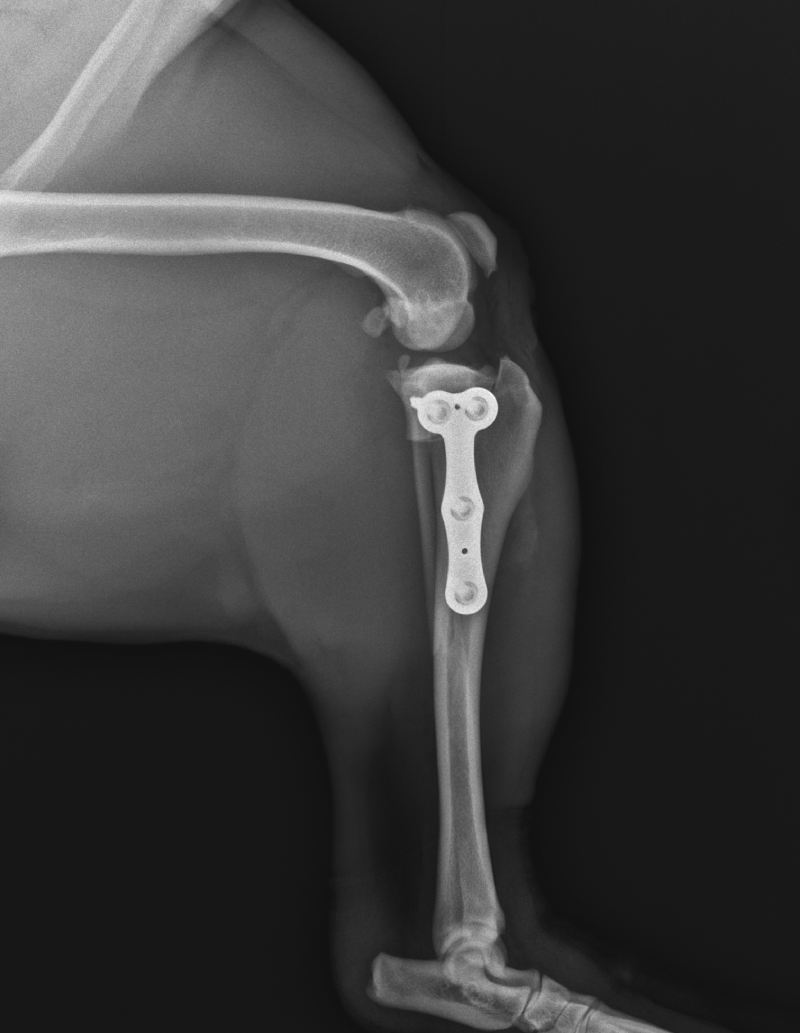

Obrázek 21: RTG snímek: Výsledek operace TPLO, obrázek vlastní

Celkově bývají komplikace během zákroku nejčastěji způsobeny chirurgem a předpokládá se, že zkušenosti chirurga, pečlivé předoperativní plánování a opatrnost během operace by měly vést ke snížení těchto problémů (19).

Základem je dále správné umístění implantátu a šroubů, které je nutné po operaci zkontrolovat RTG snímkem a v případě zjištění, že šrouby zasahují do osteotomie nebo do kloubu, ránu znovu otevřít a zrevidovat (19, 37).